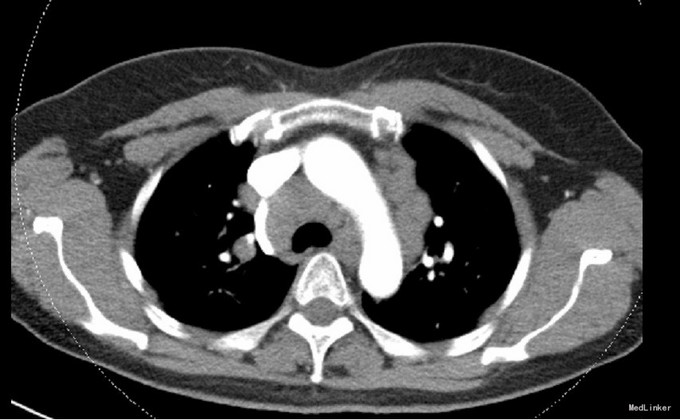

患者,女,54岁,因咳嗽1月于当地医院就诊,抗感染治疗等无效 既往无肺结核病史、无粉尘、石棉等有害物质接触病史

CT提示纵隔多发的巨大淋巴结增生,考虑结节病可能